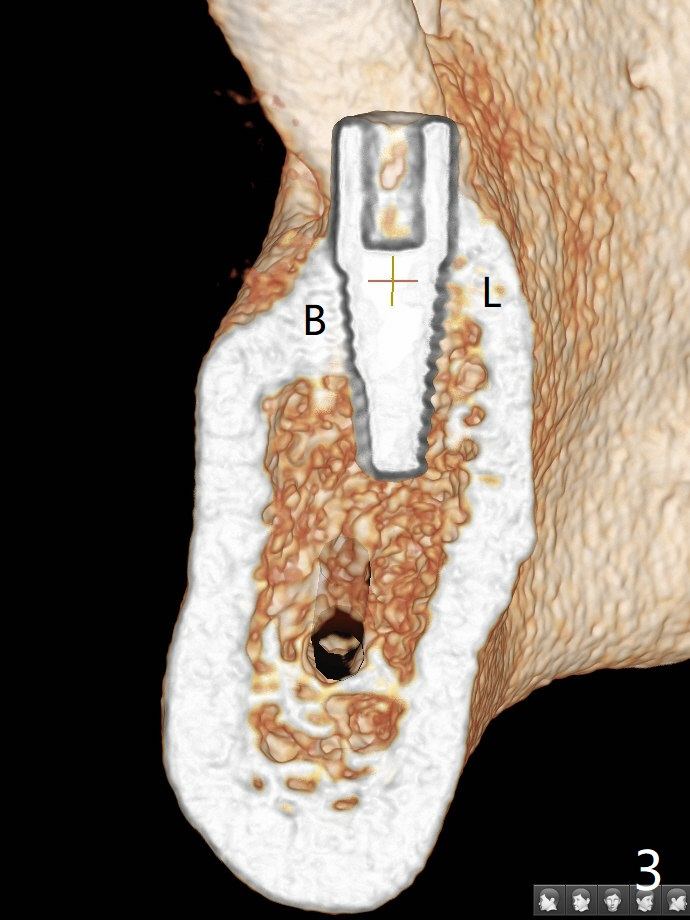

After 4x11.5 mm drill with 10.5 mm offset for bone-level implant at #19, a 4.5x14 mm tissue-level tapered tap is used with high torque. The same sized implant is placed in-completely with apical space (Fig.1 ^). Following reuse of the guide and 4.5x7.3 mm drill, the implant is placed deeper easily (Fig.2-4). The implant threads are subcrestal buccally (B (L: lingual plate), as compared to design in Fig.3'). Later the implant is placed a little deeper with insertion torque of 25 Ncm. There is no crestal bone loss 4 months postop (Fig.5). Waterlase is used for gingivectomy without anesthesia or burn after placing a 4x5 mm abutment. The access is difficult due to severe bone loss. There is no gap between the implant threads (osteointegration) 9 months postop/immediate post cementation (Fig.6 < (coronavirus)), although the crestal bone has lost. After cementation, the tooth #20 has no mobility; note bone loss around the root of #20 (Fig.5). In spite of the residual cement, there appears no bone loss 2 months postop (Fig.7). Instead the distal crestal bone is more organized.